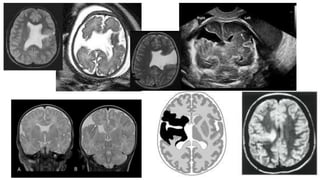

Editor's Notes

• #22 Figure 2 Patient 15. (a) Midsagittal transvaginal ultrasound image at 28 weeks showing thick and echogenic corpus callosum (arrows), and large cavum septi pellucidi (CSP) and third ventricle (3V). Inset (b) Normal corpus callosum at the same gestational age. (c) Midsagittal magnetic resonance image taken 2 days later showing the abnormal callosal genu and splenium (arrows). Note that the body of the corpus callosum is not well depicted in this image (small arrow). The serrated pattern of the parietal cortex (arrowheads) is indicative of the presence of polymicrogyria.

• #26 Figure 3 Patient 5, hemimegalencephaly. (a) Axial transabdominal ultrasound image at 28 weeks showing asymmetrical brain hemispheres with unilateral ventriculomegaly, and abnormal cortex and Sylvian fissure (arrow). (b) Sagittal plane obtained during the same examination showing frontal bossing and thick corpus callosum (arrows). (c) Fetal and (d) neonatal magnetic resonance images showing the abnormal cortex of both hemispheres and thick frontal cortex with polymicrogyria (arrows).

• #34 A, Axial SS-FSE T2-weighted image in a fetus at gestational week 27 demonstrates multiple abnormal infoldings of the developing cortex (white arrow) for expected gestational age, consistent with polymicrogyria. Areas of cystic encephalomalacia with hemorrhage (black arrow) are also seen. B, Low signal intensity consistent with intraventricular hemorrhage is also seen layering in the temporal horns bilaterally (arrowhead). Fetus was referred for ventriculomegaly and choroid plexus cysts detected on prenatal sonogram.